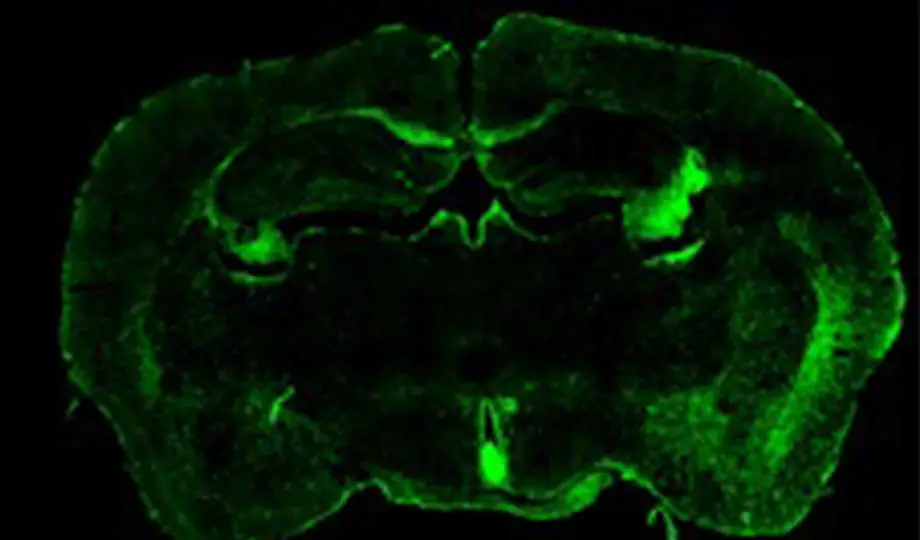

Main image: courtesy of Dr SK Singh, Gottingen Medical Centre, Germany